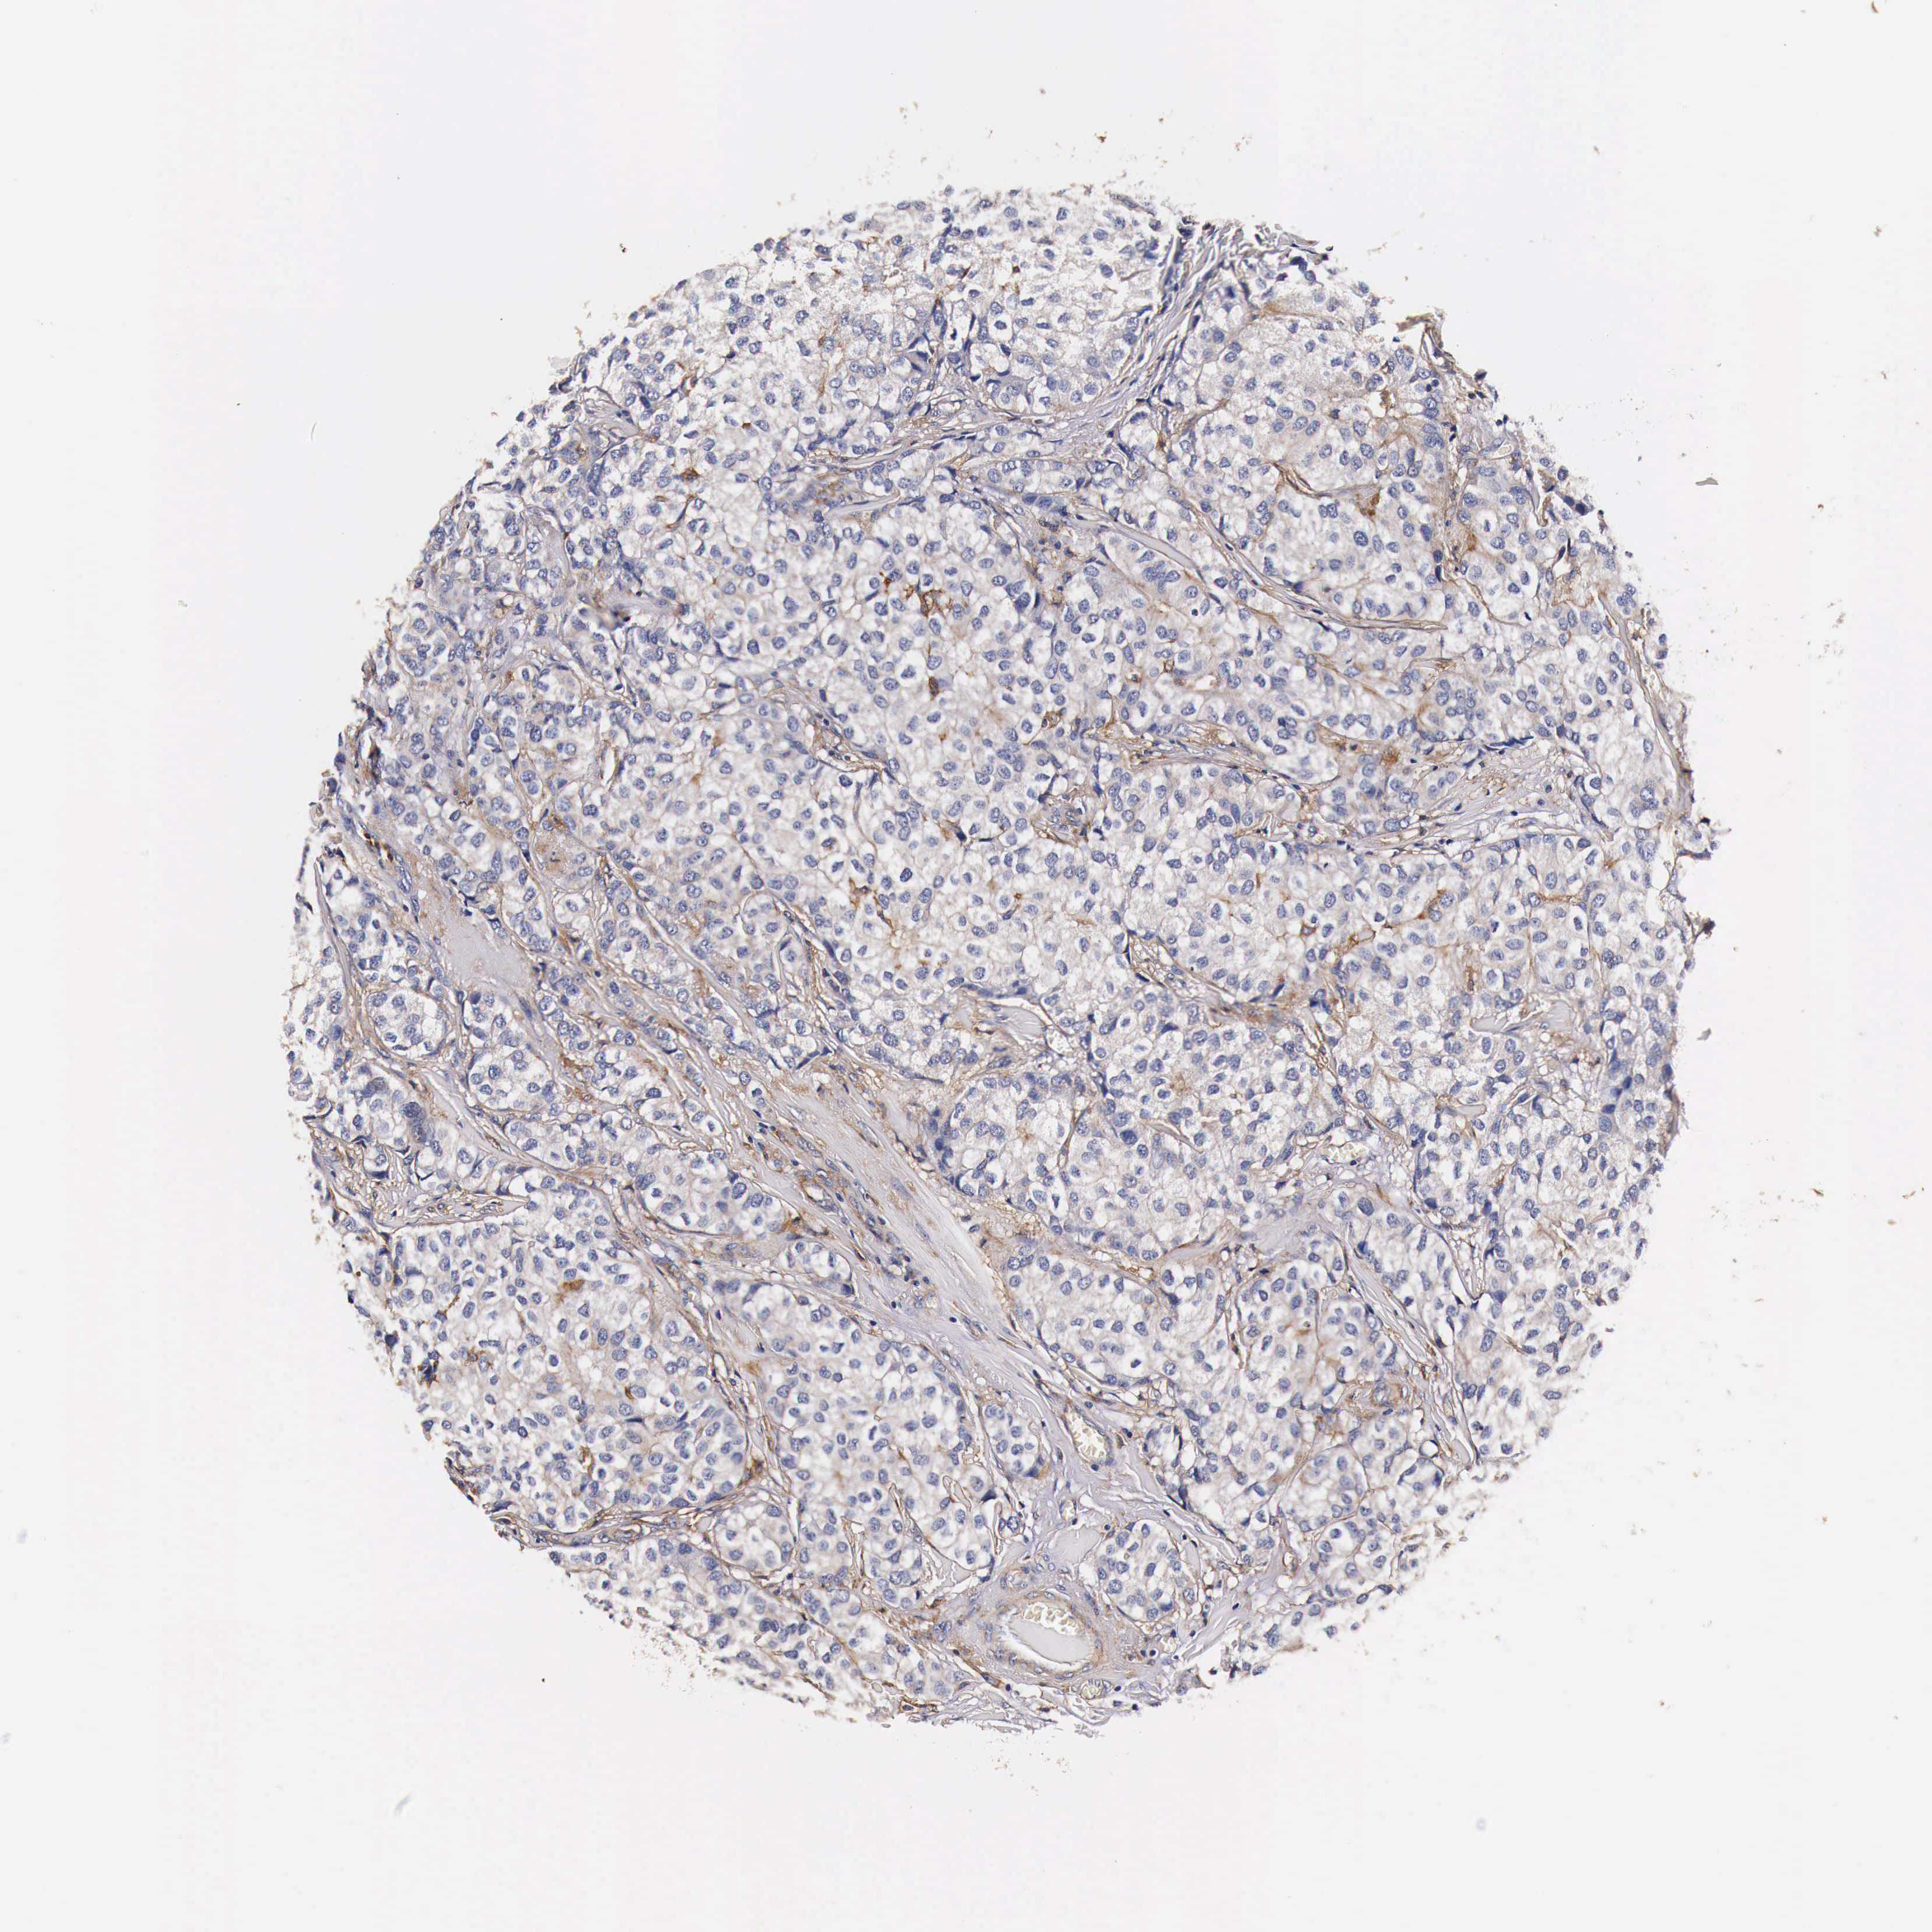

CANCER BREAST CANCER Show tissue menu

BRCA TCGA BRCA VALIDATION PROTEIN EXPRESSION